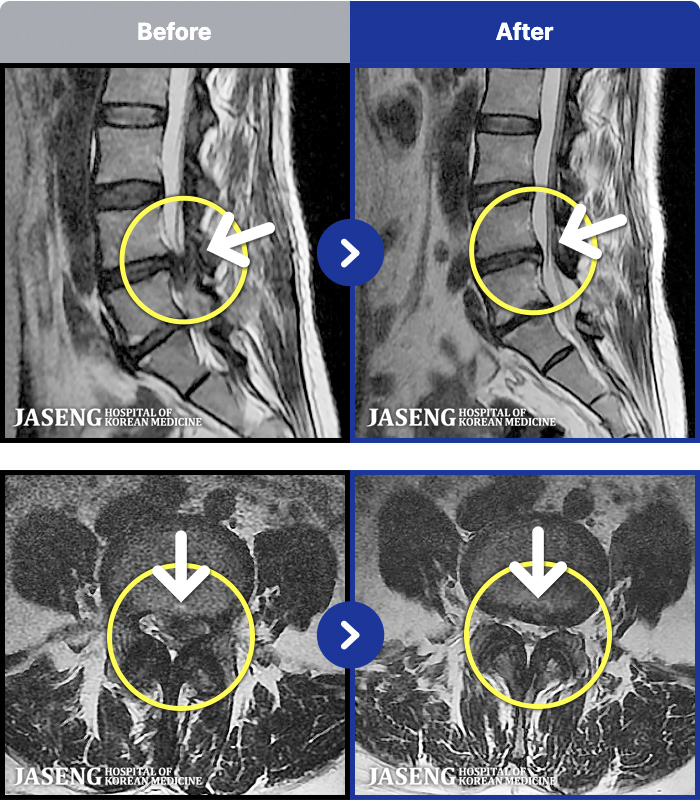

1,257 MRI ũ ʸ Ȯϼ.